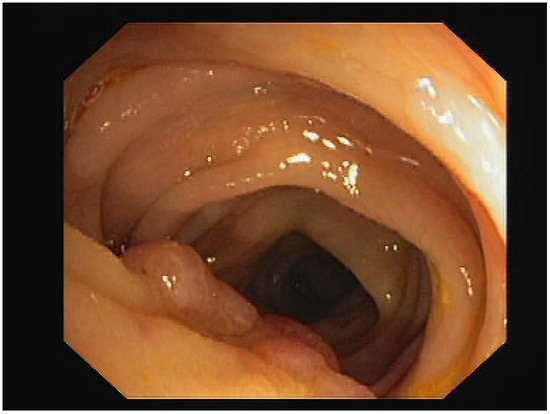

As an experiment, we focused on testing one type of the previously presented GAN methods on a dataset containing medical images. The name of the dataset is CVC-ClinicDB [28] and it is a dataset with 612 images with a resolution of 384 × 288, extracted from the video of a colonoscopy. The dataset was created by the Computer Vision Center, Barcelona, Spain, based on data from The Clinic Hospital of Barcelona. We chose to generate new enhanced resolution images, using different variations of the ESRGAN, with the purpose of finding out how the distribution of the image would differ. First, we generated an image with increased resolution, using the GAN, then, we resized the image to the original size, and finally, we plotted the distribution of the image in comparison to the original one. To do this, we plotted a histogram containing the frequency of the pixel values from 0 to 256.

For our experiments, we first used an ESRGAN. Compared to the original SRGAN, it contains a deep neural network that uses residual-in-residual dense blocks, instead of the batch normalization layers. The idea is to generate some new images with their resolution increased (1152 × 1536) and then resize them to the original dimension of the image (288 × 384). The objective is to obtain similar looking images, so that the discriminator is performing its role well, but we do not need the images to have exactly the same distributions, hence the goal is to obtain some new data. It can be seen in Figure 1 and Figure 2 that the distributions of the original image and the generated image are similar, but not identical.

Figure 1.

Original image histogram.

In Figure 1 and Figure 2, the image pixel distribution for the original image and the ESRGAN generated image can be observed.